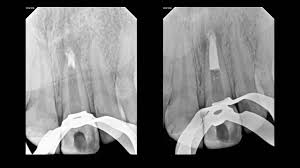

MTA Apexification

Apexification is a procedure used for immature permanent teeth with open root ends due to trauma or decay. MTA (Mineral Trioxide Aggregate) is applied inside the root canal to stimulate the formation of a hard tissue barrier at the root tip. This procedure helps stabilize the tooth and prepares it for a root canal. Apexification is crucial for young patients to prevent premature tooth loss and maintain proper jaw development.

MTA Apexogenesis

Apexogenesis is a procedure done in young permanent teeth with an incompletely formed root. When the pulp is injured but still healthy, MTA is applied to encourage the continued development of the root and the closure of the root tip. Unlike apexification, which creates an artificial barrier, apexogenesis allows the root to mature naturally, making the tooth stronger and more resistant to fractures.